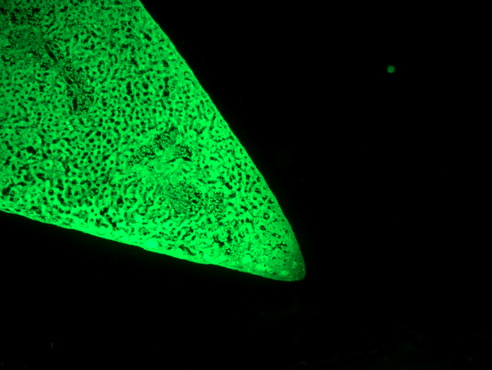

倒置荧光显微镜 MF52-N 应用于卵母细胞观察,可以直观地观察卵母细胞的大小、形态和染色体分布情况。同时,还可以通过荧光染色技术,观察卵母细胞内部的荧光信号,了解它们的生理过程和基因表达情况。通过对卵母细胞的观察和研究,可以更好地了解生殖系统的工作原理和人类健康的基本原理,为生殖医学和生命科学的研究提供重要的支持。

卵母细胞.jpg